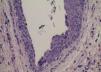

Hidrocystoma is a benign tumor originating from the apocrine gland, being an adenoma of this gland, unlike the eccrine hidrocystoma that results from a ductal dilatation by retention of secretions. It presents as translucent, round, small, painless vesicles with fluid content in their interior.1 Traditionally, they are divided into solitaries (Smith type) and multiples (Robinson type).2 Clinical differences that help in their diagnosis are: apocrine is usually solitary, larger, with a bluish color, although translucent and generally located on the face, especially on the lower palpebral region (cysts of Moll's glands) near the cilia and lacrimal drainage pathway; eccrine may be solitary or multiple, may increase with heat and decrease in the cold, translucent or opaque, with a more frequent location, on the lower eyelids but above the palpebral skin.3 They are also found on other regions such as ear, trunk, scalp, and upper limbs. Generally, they occur in adults, especially females, after the 4th decade of life. The case reported is of a 62-year-old male, white patient, who sought a dermatology clinic with the following complaint: "lumps on the face for more than five years." At the dermatological examination, there were skin-colored papules and nodules on the periocular region, with a shiny surface, translucent appearance and rare telangiectasias (Figure 1 and 2). An excisional biopsy of a nodule was performed and the histopathological examination showed a cystic lesion with a thin layer of cuboidal epithelial cells with apocrine features and amorphous liquid content, with no signs of malignancy (Figure 3). Surgical excision of the lesions was scheduled, but patient did not return to the service.

Its pathogenesis seems to result from obstruction of the sweat duct just above the glandular groove (deep dermis) due to an inflammatory process or trauma. The diagnosis is initially clinical, followed by histological confirmation. Histologically, apocrine hidrocystomas are unilocular or multilocular dermal cysts with one or more layers of epithelial cells showing bulbous protrusions and luminal secretion by decapitation.4 It may also have papilliferous projections, being covered by two layers of secretory cells. The inner cells are columnar and show eosinophilic cytoplasm with typical bulboapical expansions.